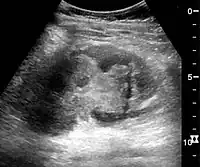

In medical imaging, the acute changes in the kidney are often examined with renal ultrasonography as the first-line modality, where CT scan and magnetic resonance imaging (MRI) are used for the follow-up examinations and when US fails to demonstrate abnormalities. In evaluation of the acute changes in the kidney, the echogenicity of the renal structures, the delineation of the kidney, the renal vascularity, kidney size and focal abnormalities are observed.[16] CT is preferred in renal traumas, but US is used for follow-up, especially in the patients suspected for the formation of urinomas. A CT scan of the abdomen will also demonstrate bladder distension or hydronephrosis.

Renal ultrasonograph in renal failure after surgery with increased cortical echogenicity and kidney size. Biopsy showed acute tubular necrosis.[16]